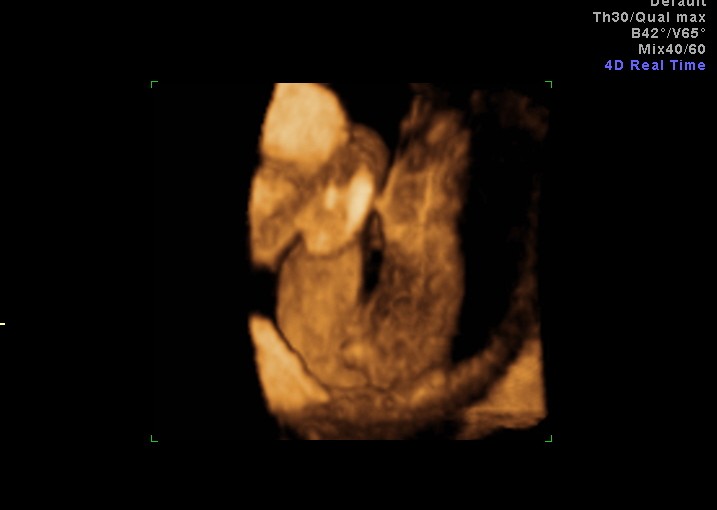

3d Ultrasound 17 Weeks Girl

This shot at 17 weeks is from the bottom where you can see the labia marked as a baby girl by the ultrasound technician.

The girl ultrasound gallery is designed to show you what a baby girl looks like on ultrasound photos from various weeks of pregnancy. Here is our little girl at 17 weeks 1 day. 3d ultrasound 17 weeks girl a new conception 3d ultrasound studio genderwmv duration. Found out at 20 weeks its a girl.

At 17 weeks it should be possible to determine sex unless the ultrasound technician wasnt able to get a good view. Us says 15 weeks but at the end of the us it is recalculated to 16 ga. In all four of my pregnancies gender was very clear by 16 17 weeks. 16 weeks pregnant full ultrasound of baby boy.